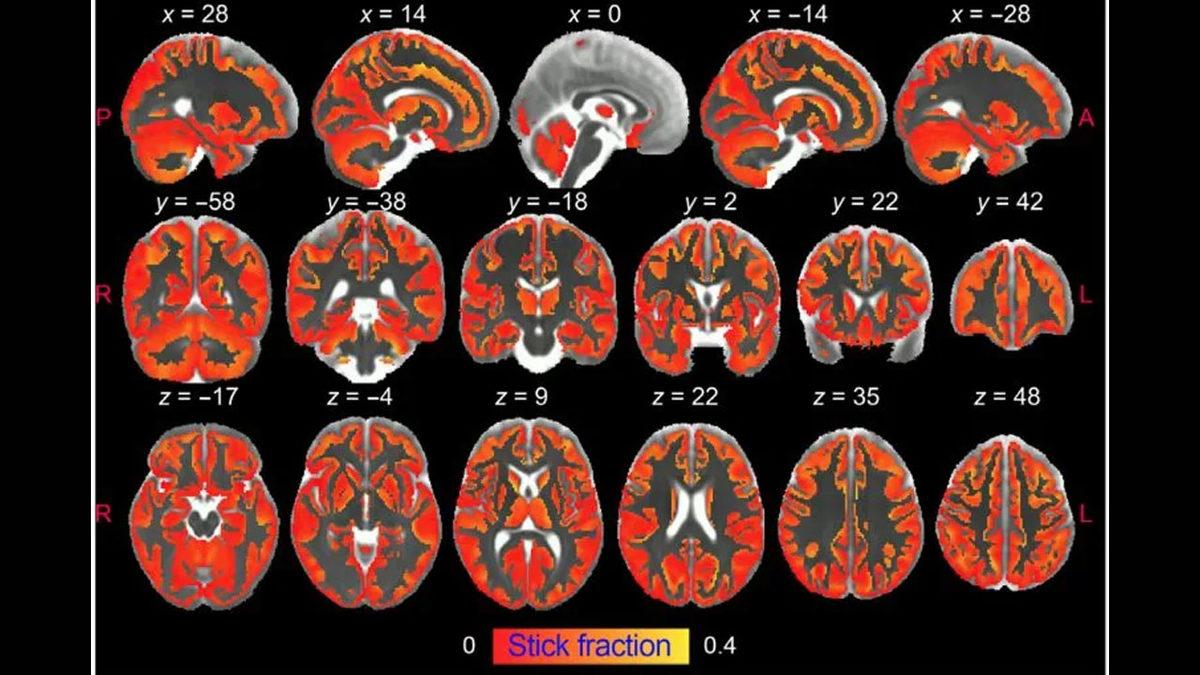

Teknolojinin gelişimiyle tıp dünyasında her geçen gün bir ilke imza atılırken, bugün o ilklerden birisi daha geldi. İspanya’daki Nörobilimler Enstitüsü’nden uzmanlar, tarihte ilk kez beyindeki sinir dokusunun iltihaplanması durumu olan ‘nöroinflamasyon’u görüntülemeyi başardı. Üstelik enfeksiyon, yüksek detay ile gözlemlendi.

Nöroinflamasyon, normal şartlarda MRI cihazı ile görüntülemezken uzmanlar bu noktada özel bir sürece başvurdu. Uzmanlar, difüzyon ağırlıklı MRI’ın nöroinflamasyonun kaynağında bulunan iki tür beyin hücresi olan mikroglia ve astrositlerin aktivasyonunu ve gelişimini farklı bir şekilde tespit edebildiğini keşfetti.

Uzmanların yenilikçi bir yöntem ile mümkün kıldığı yeni keşif, parkinson, Alzheimer ve Huntington hastalıkları gibi nörodejeneratif hastalıkların araştırma ve gidişatını değiştirmek için ilk temel olma potansiyeli taşıyor. Zira bu hastalıkların kaynağı ve ilerlemesini sağlayan nedenlerden birisi de söz konusu iki beyin hücresinin sürekli aktivasyonu ile ortaya çıkan kronik inflamasyon.

Bunun yanı sıra uzmanlar, yeni geliştirdikleri tekniğin her iki koşulun da ayırt edilebilmesi için nörodejenerasyonlu ve nerodejenerasyonsuz iflamasyonu saptamak için hassas ve spesifik olduğunu gösterdi. Son olarak tekniğin multipl skelerozun (MS hastalığı) inflamasyon ve demiyelinizasyon özelliklerini ayırt etmeyi mümkün kıldığını paylaştı.